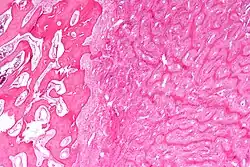

| Micrograph showing fibrous dysplasia with the characteristic thin, irregular bony trabeculae and fibrotic marrow space. H&E stain. | |

Fibrous dysplasia is a mosaic disease resulting from post-zygotic activating mutations of the GNAS locus at 20q13.2-q13.3, which codes for the α subunit of the Gs G protein-coupled receptor.[13] In bone, constitutive Gsα signaling results in impaired differentiation and proliferation of bone marrow stromal cells.[14] Proliferation of these cells causes replacement of normal bone and marrow with fibrous tissue. The bony trabeculae are abnormally thin and irregular (bony spicules on biopsy).